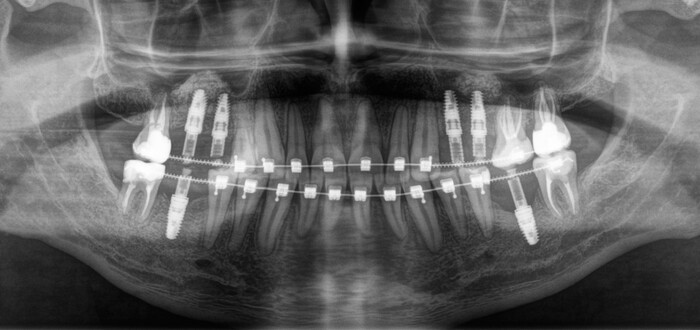

После недолгой беседы и осмотра

Роману было предложено сделать компьютерную томографию для более детальной диагностики и составления комплексного плана лечения.

На снимке видно, что он следил за зубами, занимался лечением, но в определенный момент что-то пошло не так. После проведения совместной консультации со всеми смежными специалистами (ортодонтом, ортопедом, терапевтом) пациенту был предложен комплексный план лечения, который включает в себя:

- удаление остаточных корней зубов, которые не подлежат восстановлению

- лечение и/или перелечивание зубов, которые в этом нуждаются

- ортодонтическое исправление прикуса

- установка имплантатов в процессе брекет-лечения

- временное протезирование на имлантатах

- постоянное протезирование на имплантатах и на жевательных зубах, которые ранее были

пролечены эндодонтически (в которых удалили нервы).

После удаления, лечения и начала ортодонтии прошло около 8 месяцев:

Кривые зубы раскривились, заваленные – распрямились.

После того, как все активные передвижения зубов закончены, ортодонт даёт отмашку для начала установки имплантатов.

Было принято решение начать с правой стороны:

Произведена установка 3 имплантатов и синус-лифтинг в области 5-го и 6-го зуба на верхней челюсти и 6-го на нижней. В полости рта это выглядело примерно так:

Спустя примерно 3 месяца пришла очередь левой стороны:

Также были установлены 2 имплантата и проведен синус-лифтинг на верхней челюсти (в области 5-го и 6-го зуба) и 1 на нижней (в области 6-го зуба).

После установки имплантатов достаточно 3.5 месяцев до снятия слепков и изготовления временных коронок. Изготовление коронок проходило так же в два этапа по сторонам. Я не вижу смысла добавлять много + - одинаковых картинок, поэтому вот результат с временными коронками сразу на всех установленных ранее имплантатах.

Вжух:

3.5 месяца мимолетны, как первый секс. А у кого-то и каждый последующий.

Коронок на рентгеновском снимке вы не увидите, потому что пластик не рентгеноконтрастен. Видны лишь металлические абатменты, за которые «держится» пластмассовая часть, – такие палки-переходники между имплантатом и коронкой. Временные коронки изготовлены из фрезерованной пластмассы. Пластмассовый брусок выпиливается в специальном станке и на выходе представляет собой практически готовую коронку.

В полости рта это выглядит так:

Я решил добавить фотографии сразу после снятия брекетов, а не с ними, как это было на рентгеновском снимке. Думаю, так выглядит намного симпатичнее.